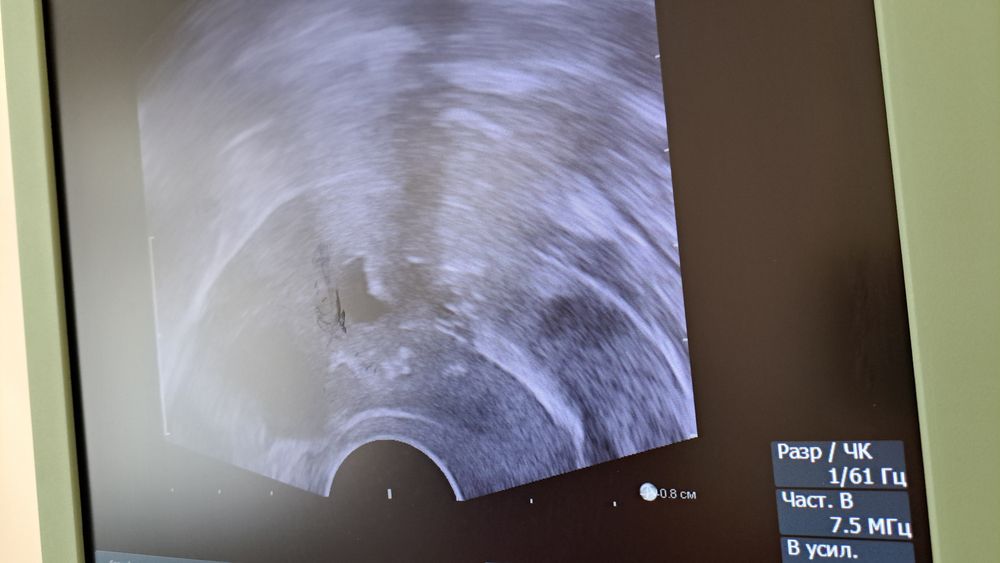

Изображение Изображение это черная жидкость, которая распределена неравномерно. видно сращение посредине. а к дну матки жидкость не попала. из за толстой синехии. поэтому и нет месячных

Изображение это вид сверху. дно матки, огромный тяж посредине.